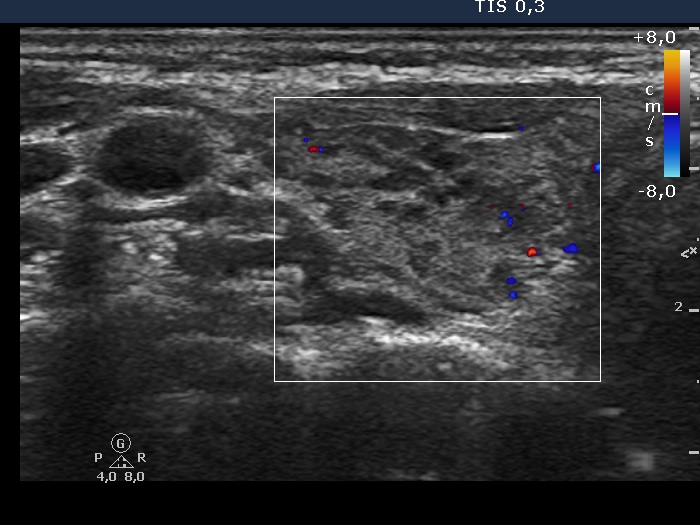

The thyroid gland is located in the neck, just above where your collarbones meet in the middle. Web chronic thyroiditis is caused by a reaction of the immune system against the thyroid gland. The disorder is also called hashimoto disease.

These antibodies cause inflammation in your thyroid gland. This disorder can be either painful or not felt at all. The thyroid gland is located in the neck, just above where your collarbones meet in the middle.

Web chronic thyroiditis is caused by a reaction of the immune system against the thyroid gland. The number of people who have hashimoto’s disease in the united states is unknown. There are four main types of thyroiditis:

Web hashimoto’s thyroiditis, also known as hashimoto’s disease, damages your thyroid function. Web hashimoto’s thyroiditis is also known as chronic lymphocytic thyroiditis or autoimmune thyroiditis. However, the disease is the most common cause of hypothyroidism, which affects about.

This means you develop antibodies [thyroid peroxidase (tpo) and/or thyroglobulin (tg) antibodies] that damage your thyroid gland. The disorder is also called hashimoto disease. The thyroid gland is located in the neck, just above where your collarbones meet in the middle.

This can last for a few weeks or months. Subacute thyroiditis is believed to be triggered by a viral infection. It often results in reduced thyroid function ( hypothyroidism ).